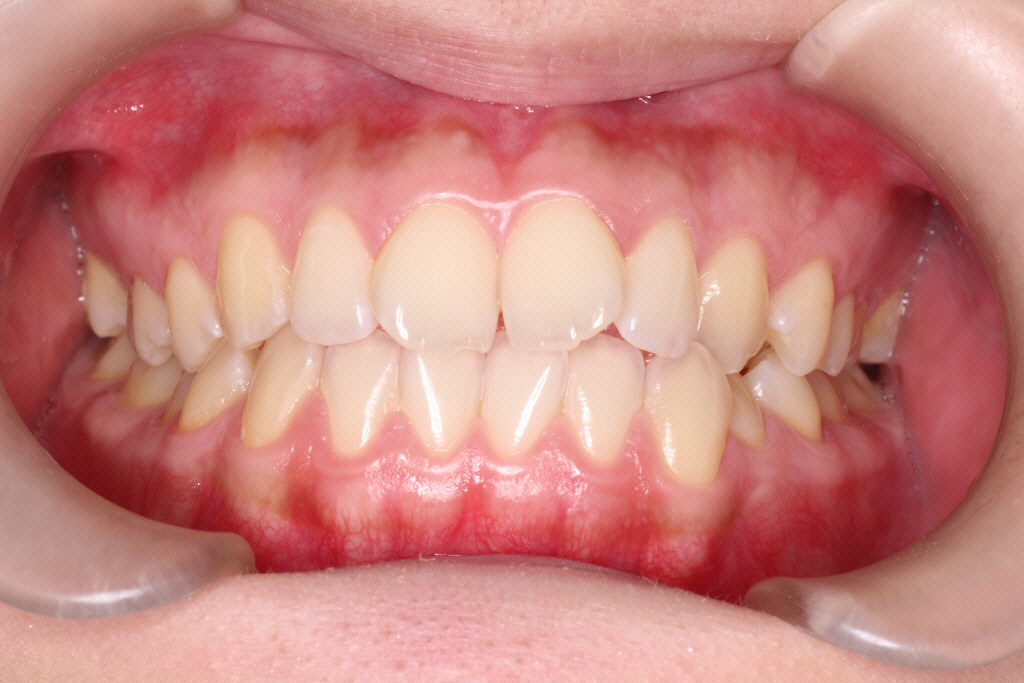

2回目のインビザラインのクリーンチェックです。最後のアライナーの12番です。

上のクリーンチェックでは前歯に隙間は空かない予定でしたが、

私は、舌癖(舌を前に出してしまう)があることがわかりました。

舌を前に出してしまうと、前歯を押してしまうためインビザラインで動かしていくときに妨げになってしまいます。